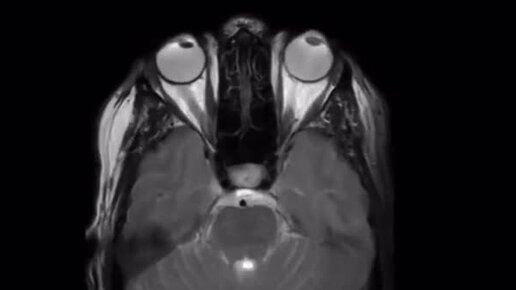

Движение глаз на МРТ